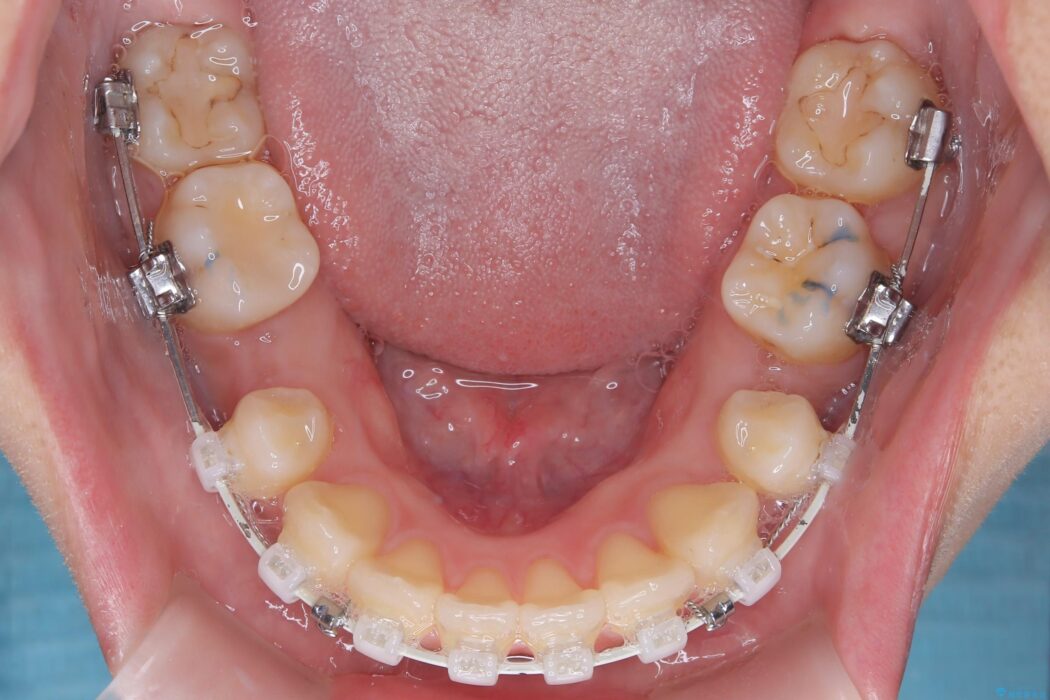

確実な歯の移動を実現するため、ワイヤー矯正装置を使用しました。

精密検査の結果、前歯を大きく後退させ、口元の突出感を改善するためには、スペースの確保が必要と診断しました。

そこで、上下左右の第一小臼歯(4番目の歯)を計4本抜歯し、そのスペースを利用して前歯全体を奥へ移動させる抜歯矯正の治療計画を立案。